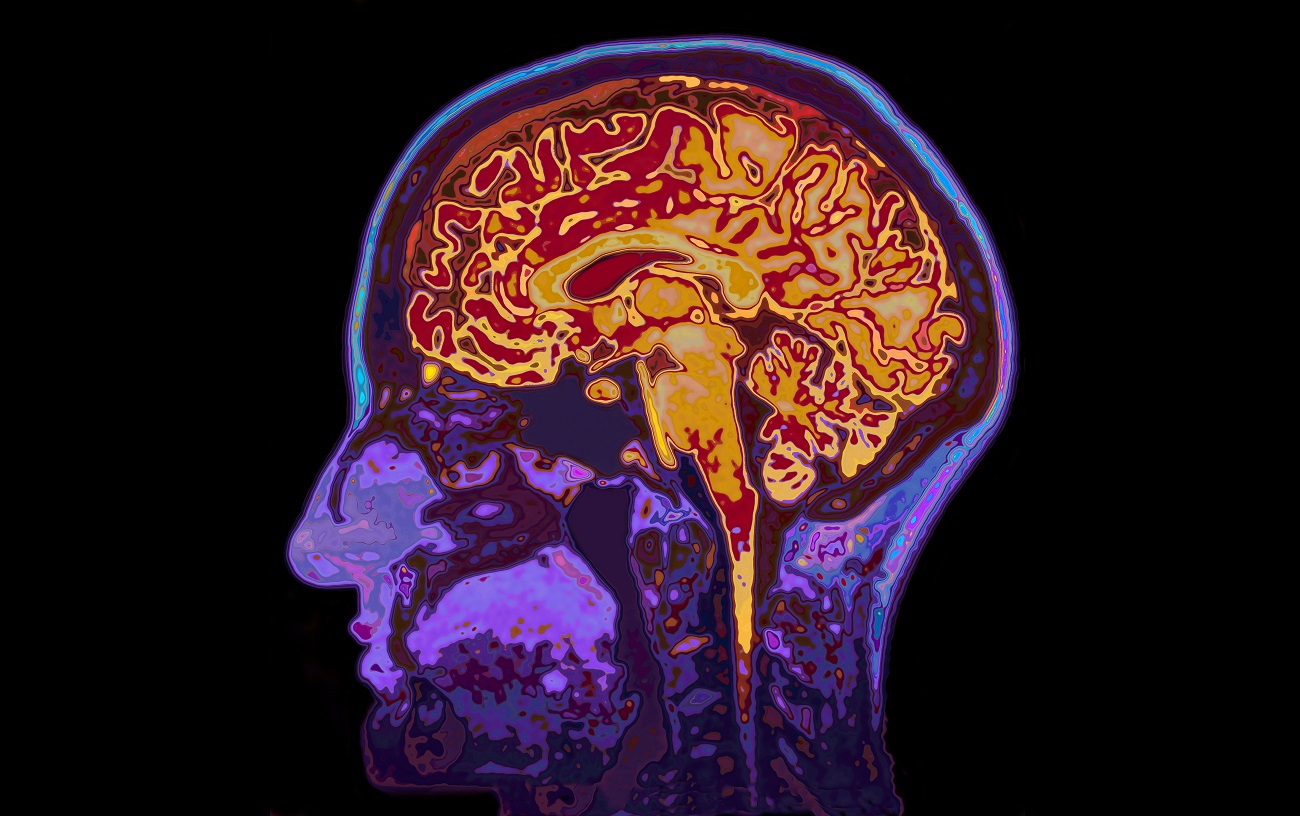

In LACI-2 patients will take cilostazol, isosorbide mononitrate or both. The researchers think that these drugs may help reduce the damage to the arteries in the brain that cause the stroke and lead to cognitive decline. They will perform MRI scans on people taking part in the trial to see what effects these drugs have on the small blood vessels within the brain.